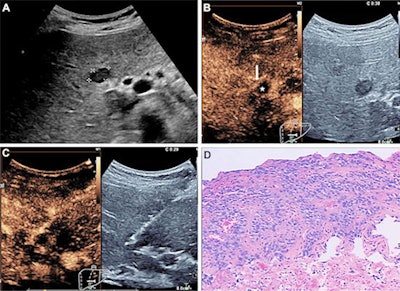

The study authors noted that the target lesions or areas were changed after CEUS in 257 cases, which they noted "likely" resulted in a higher biopsy accuracy in the CEUS-guided biopsy group. They added that CEUS can be used to identify vascularized areas of a lesion and that hypoenhancement in the late phase is a well-known CEUS pattern of malignancy.

"Thus, our data enabled us to confirm that CEUS is very helpful in the identification of accurate puncture areas and in guiding the biopsy," the team wrote. "CEUS-guided biopsy may be particularly useful in focal liver lesions with suspected necrosis."